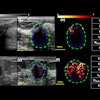

Carestream Health plans to highlight enhancements to its digital breast tomosynthesis (DBT) software module at the upcoming ECR 2015 in Vienna.

Upgrades include a slabbing tool that combines slices of a DBT series while allowing the user to choose different rendition modes and slab thicknesses; improved workflow capabilities that optimize the reading of tomosynthesis exams at the same time as other procedures; and the display of DICOM-compliant 2D synthetic views, according to the firm.